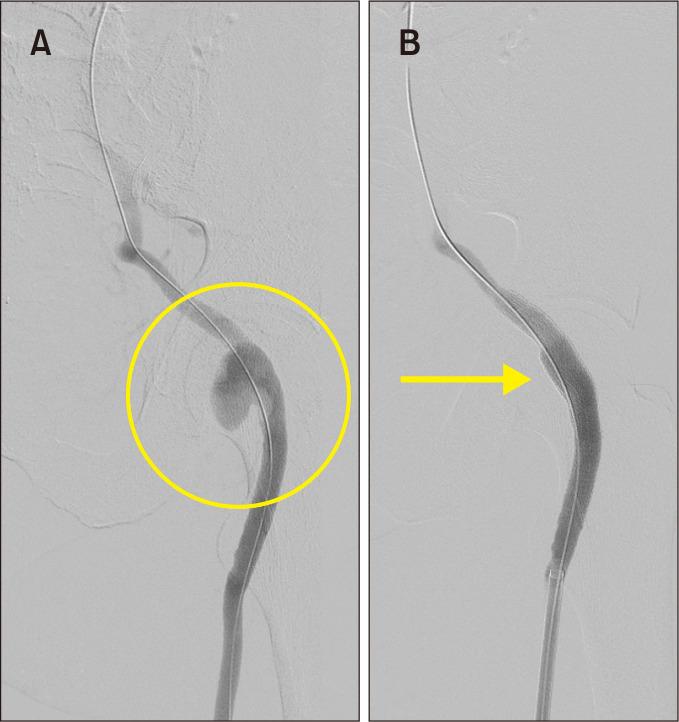

Persistent Sciatic Artery Aneurysm as a Rare Cause of Acute Lower Limb Ischemia.

Vasc Specialist Int. 2022 Mar 31;38:9. doi: 10.5758/vsi.220009.